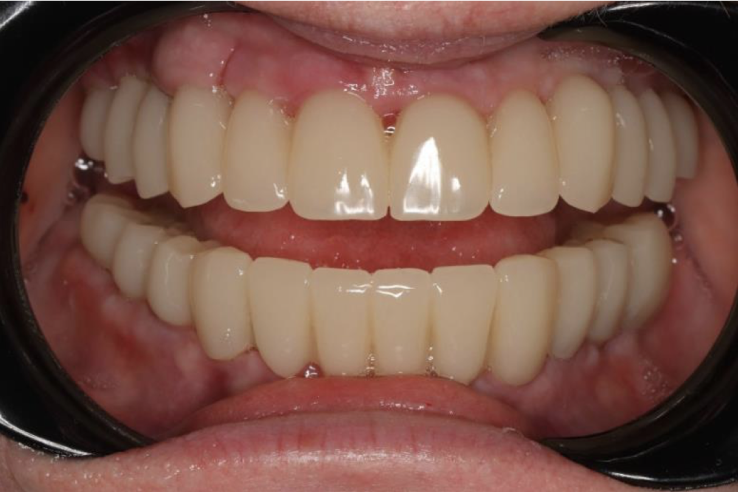

Далее была проведена та же процедура на нижнюю челюсть и вскоре уже сделаны постоянные коронки.

Готово! Полноценные зубные ряды, восстановлено жевание, кусание. Изменилось и помолодело лицо, изменилась речь. Эта конструкция не снимается, пациент пользуется ею на постоянной основе, радуясь своей новой улыбке.